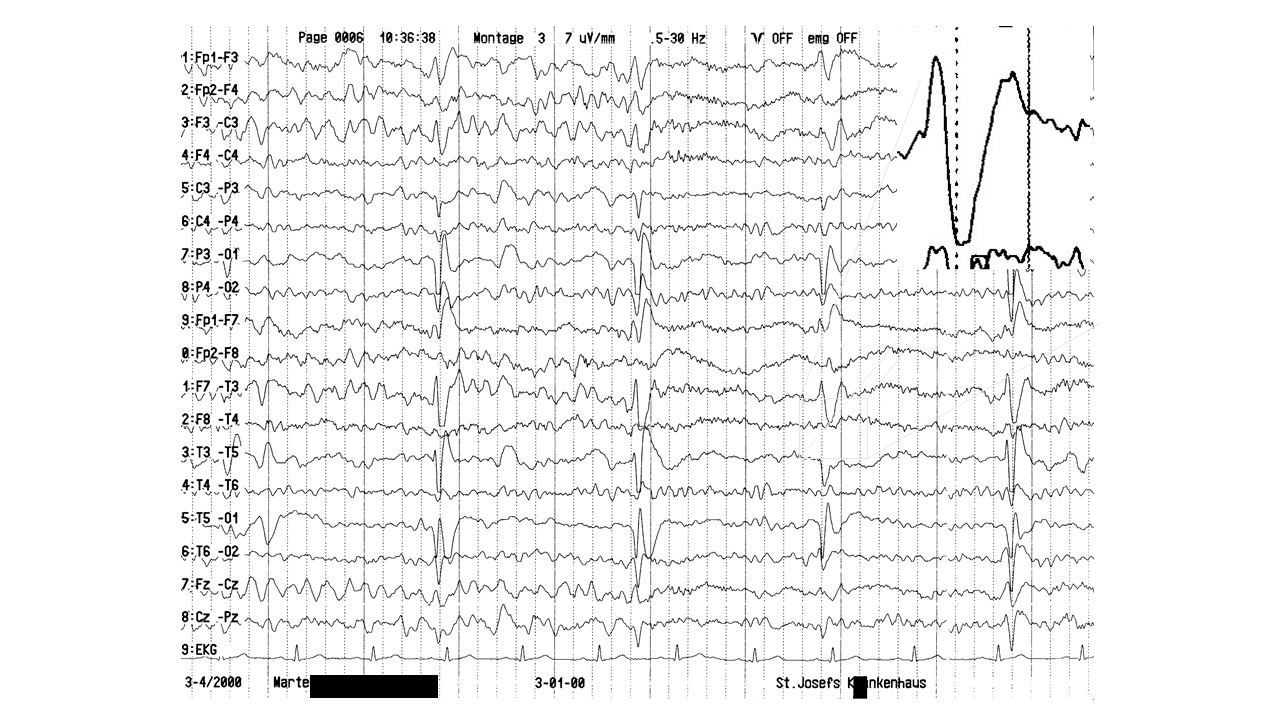

EEG-Seminar III | 68.69 zurück | weiter

folie69.jpg